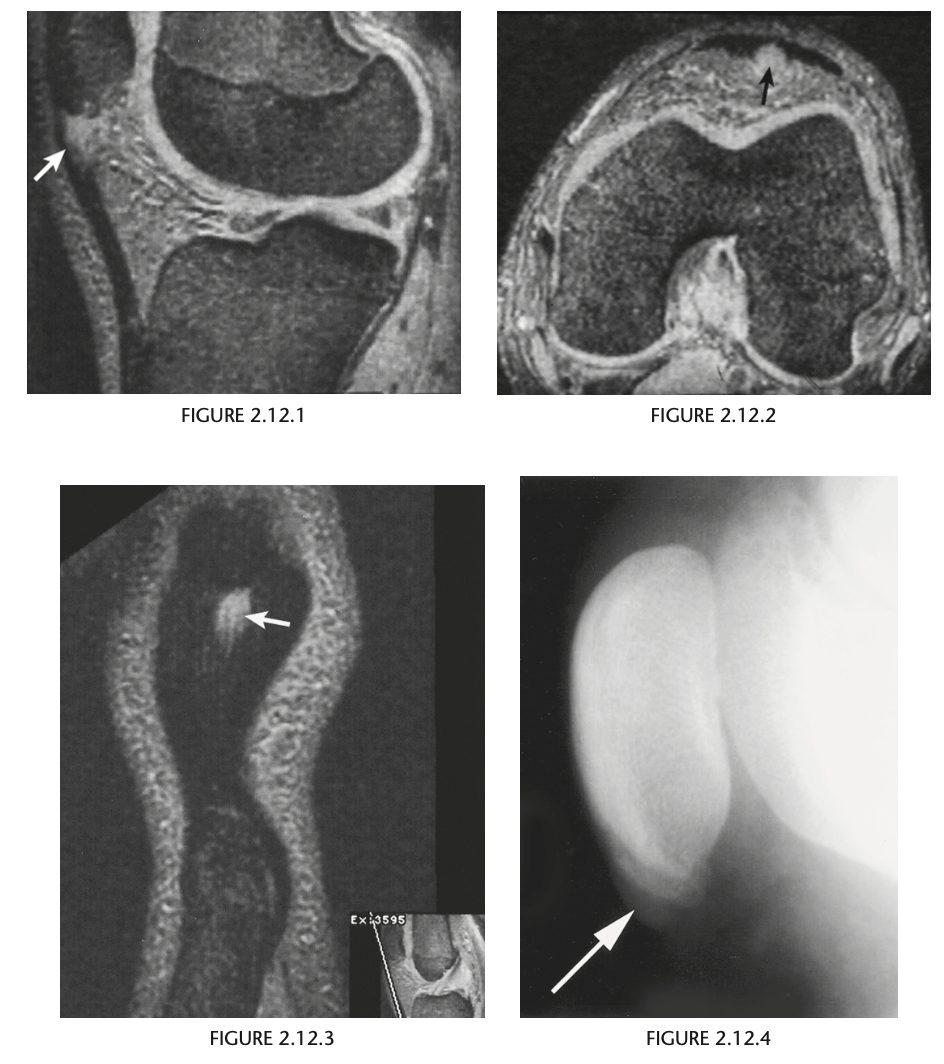

A 16-year-old basketball player with pain in his left knee

Sagittal, axial and coronal gradient-recalled echo MR images of the left knee

show a focal area of high signal intensity within the

patellar tendon just below its origin from the infe-

rior aspect of the patella (arrows)

Patellar tendionosis

Overuse syndrome. Chronic repetitive stress without rest may

result in necrosis, fibrosis, and degeneration within

the tendon and may over time lead to tendon rup-

ture.

Sindig-Larsen-Johansson disease = Bony fragmentation of the lower pole of the patella in a young patient. (Osteochondroses)

Figure 2.12.4 is a coned-down,

lateral knee radiograph of a 13-year-old athlete

with anterior knee pain and shows fragmentation

of the inferior pole of the patella (arrow). The sagit-

tal T2-weighted MR image (Fig. 2.12.5) confirms the fragmentation of the patella and shows prepatel-

lar edema and edema within the proximal patellar

tendon (arrow). The sagittal T1-weighted MR image

(Fig. 2.12.6) shows the fragmentation of the patella

that is characteristic of this disorder (arrow).

MRI is the diagnostic investigation of choice to

confirm the clinical suspicion of patellar tendinosis.